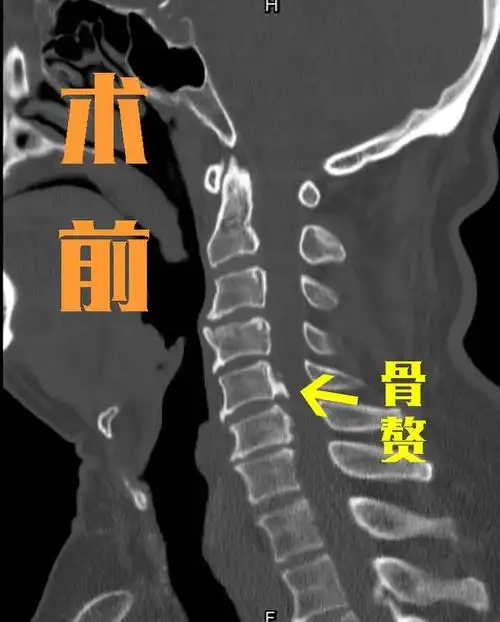

颈椎骨质增生是怎么回事

颈椎为什么会长骨刺,骨质增生?

颈椎病做前路手术更好?若后方骨质增生,还能做前路手术吗?